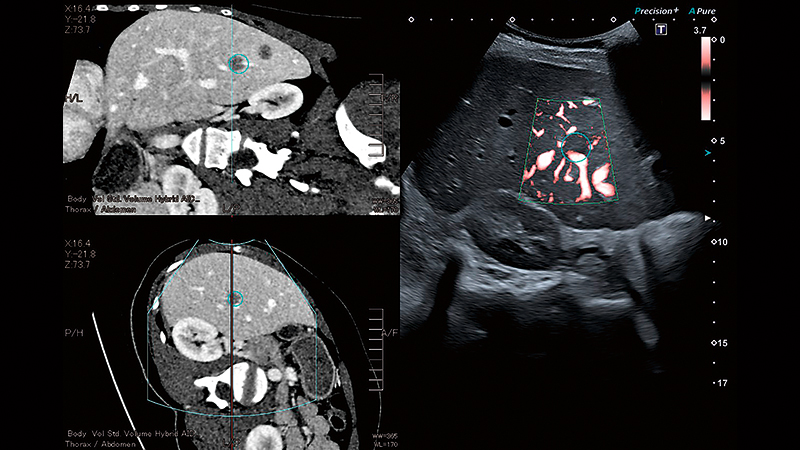

Складні інтервенційні втручання

Спеціалізовані датчики, інструменти візуалізації та навігації системи Aplio допоможуть вам виконувати інтервенційні процедури та подальше спостереження ефективно та впевнено.